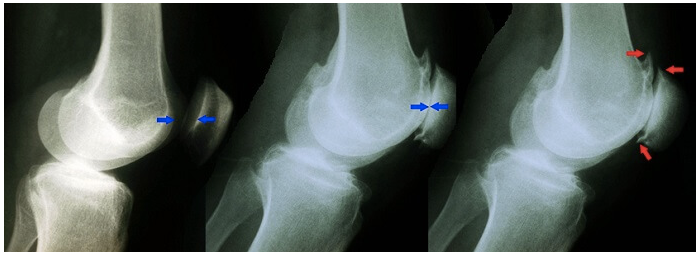

На рентгенограммах коленных суставов характерные для артрозов изменения: сужение суставной щели, деформация и разрушение основного вещества хряща и кости, краевые остеофиты, кисты прилегающих частей костей.

К числу ранних рентгенологических признаков гонартроза бедренно-надколенникового сочленения относятся заострения межмыщелковых бугорков большеберцовой кости и надколенника. Наблюдаются также мелкие эрозии в нижней трети задней поверхности надколенника, сужение щели между надколенником и бедренной костью и остеофиты на верхнем и нижнем краях надколенника.

Рентгенограммы здорового коленного сустава (слева) и сустава при гонартрозе бедренно-надколенникового сочленения. Среднее изображение показывает потерю суставной щели. На правом изображении выделяются образующиеся костные заострения или шпоры.

При гонартрозе бедренно-большеберцового сочленения часто поражаются суставные мениски, особенно медиальный. Это приводит к резкому сужению суставной щели или к деформациям конечностей.